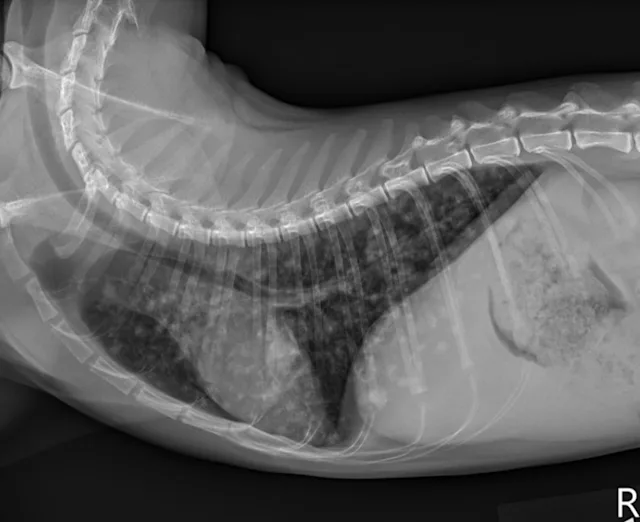

Butorphanol (0.2 mg/kg IV) was administered for sedation to obtain 3-view thoracic radiographs (left lateral, right lateral, ventrodorsal). Results revealed diffuse pulmonary nodular changes with an underlying bronchointerstitial pattern (Figure 1). Fungal pneumonia, parasitic pneumonia, neoplasia, and eosinophilic inflammatory disease were the most likely differentials for this pattern.

A

FIGURE 1 Left lateral (A), right lateral (B), and ventrodorsal (C) thoracic radiographs at the time of initial diagnosis. Diffuse pulmonary nodular changes with an underlying bronchointerstitial pattern can be seen.